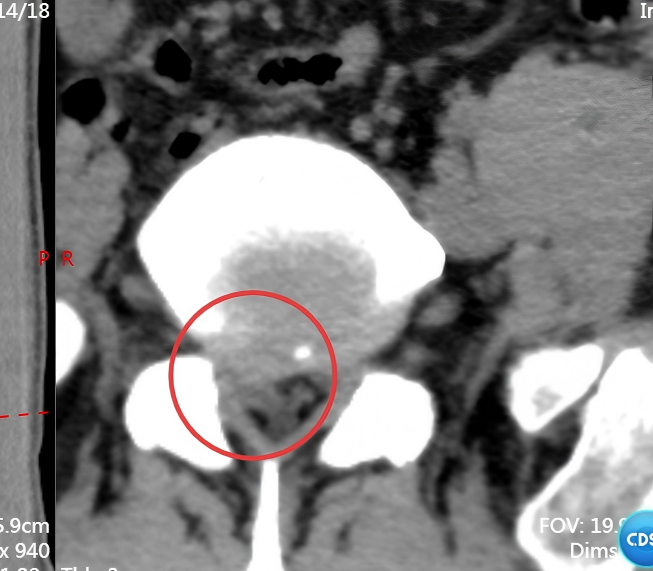

51 岁的李先生(化姓)因重物砸伤致腰部剧痛,被送到医院时,他双下肢麻木无力。检查显示,李先生的伤情极为复杂:L1 椎体呈屈曲 - 牵张型骨折,骨折块移位凸入椎管并出现硬膜外血肿,压迫脊髓,同时合并 T12、L2、L3、L4 多节段椎体骨折,L2-L4 双侧横突骨折,还伴有多发肋骨骨折及血气胸。医生指出,脊髓长期受压可能导致下肢瘫痪等不可逆后遗症,需立即手术干预。

脊柱外科满孝旭副主任医师带领手术团队针对李先生多节段脊柱骨折的特点,制定了精准的手术方案。术中,医生在全麻下为他实施 T12-L5 骨折切开复位内固定术,通过精准植入内固定器械,逐一矫正移位的椎体,重建脊柱正常序列与稳定性;同时仔细清除椎管内血肿,解除脊髓压迫,全程兼顾创伤控制与神经保护。

术后复查 CT 显示,李先生脊柱序列恢复良好,内固定位置精准,稳定性得到有效重建。